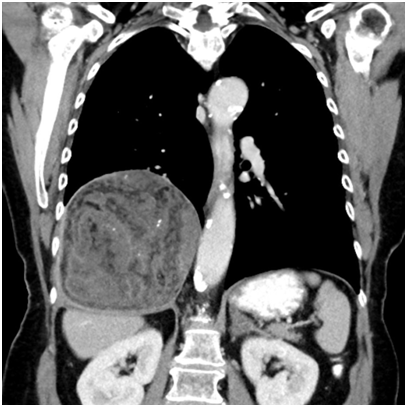

A 74-year-old female patient presented with symptoms of upper respiratory tract infection and mild progressive shortness of breath. She had a history of smoking, chronic obstructive pulmonary disease (COPD) GOLD stage 2 and arterial hypertension. A routine X-ray examination of the chest revealed elevation of the right lung. Subsequent computed tomography showed a large heterogenous tumor measuring 14x12x11cm above the right diaphragm, partly fatty and with calcifications. PET-tomography findings were similar and there was no contrast uptake. The radiological differential diagnoses included a pleural fibrous tumor owing to the proximity of the lesion the diaphragm as well as teratoma and low grade liposarcoma considering its partly fatty aspect. Due to the size of the lesion the possibility of a hamartoma was not considered at the time.

Figure 1 Radiologic imaging (CT) showing a large heterogeneous lesion in the lower right thoracic cavity.